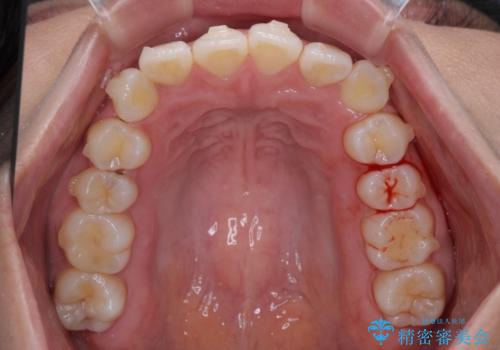

- 前歯のデコボコを治したいとのことで来院された患者様です。

上下顎ともに歯列全体の後方移動とIPR(歯と歯の間を削る)によってデコボコが解消するように設計し、インビザラインにより治療を行うこととしました。

上下ともにIPRを積極的に行っているため、舌の突出癖をしっかりと改善できないと、後戻りにより隙間やデコボコが早い段階で発現することになるため、舌のトレーニングが非常に大切になります。